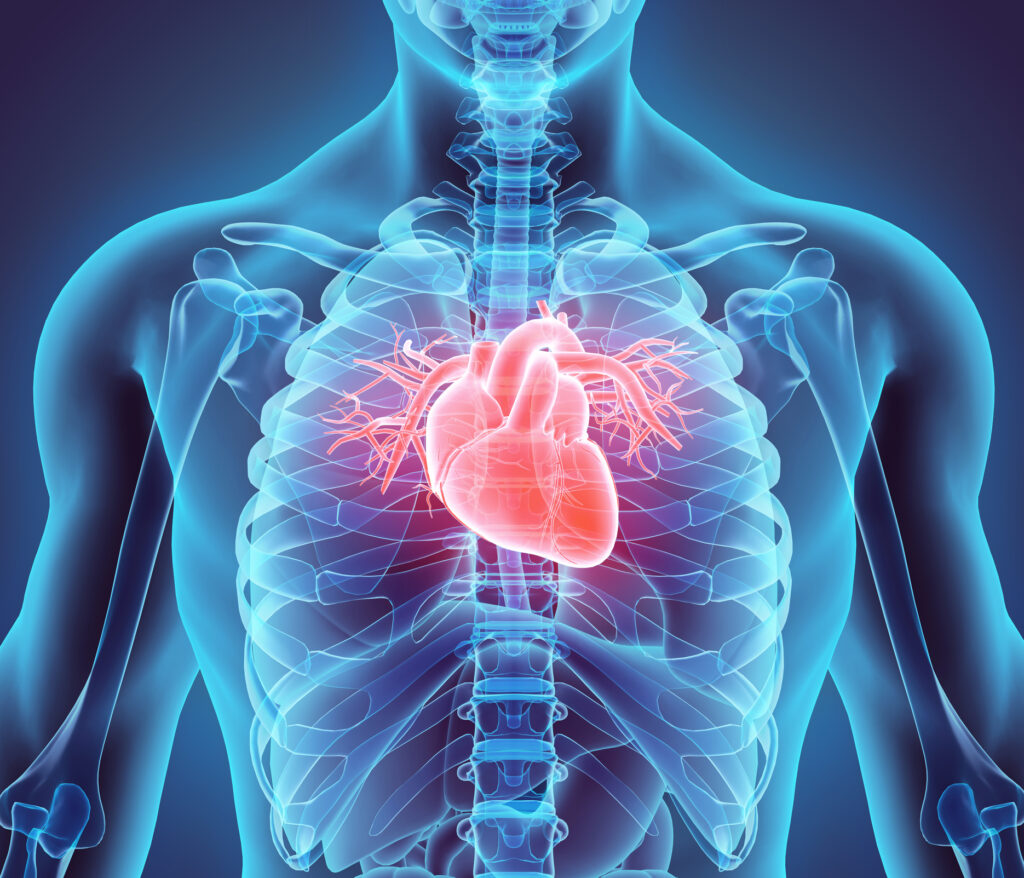

Egészen konkrétan arra leszünk kíváncsiak, mennyire figyeltél akkor, amikor az emberi testet vettük. Ha az első sorban ülve jegyzeteltél, vagy utánaolvastál a témának a suli óta, akkor lazán fogod venni az akadályt!